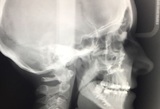

La programmazione dell’intervento chirurgico deve prevedere una stretta collaborazione tra chirurgo maxillo-facciale e ortodontista. La fase preoperatoria si conclude con la determinazione, mediante appositi software, del V.T.O. (Visual Treatment Objective) chirurgico in cui si stabiliscono le correzioni da eseguire sui singoli segmenti ossei. L’analisi cefalometrica, gli esami fotografici e radiografici (spesso Cone Beam TC), la valutazione dei modelli in gesso delle arcate dentarie consentono di delineare con precisione millimetrica gli spostamenti e/o le rotazioni dei vari segmenti scheletrici che saranno eseguiti in sede intraoperatoria.

Generalmente il trattamento ortodontico e chirurgico combinato richiede circa 18-24 mesi ed il protocollo diagnostico-terapeutico deve avvalersi di esame obiettivo, fotografico, radiografico, cefalometrico ed esame dei modelli in gesso delle arcate dentarie.